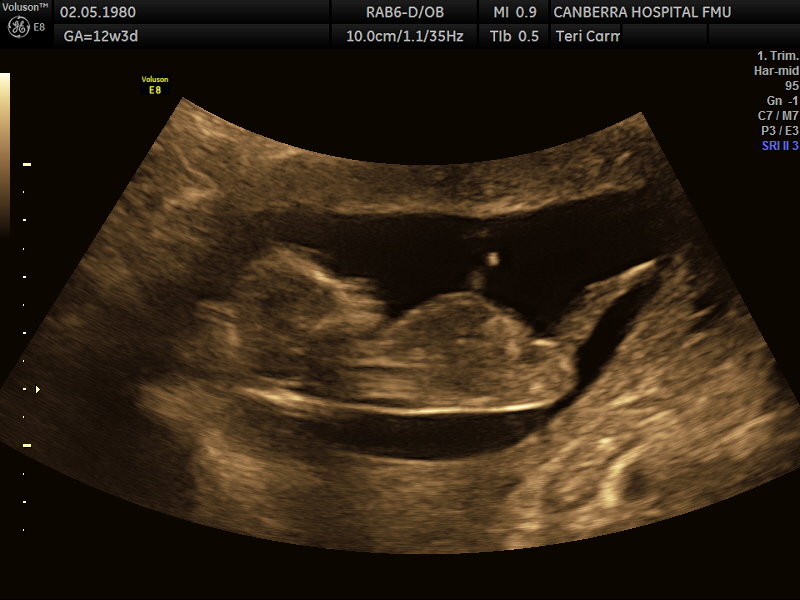

Its been ages once I've been on here but I'm back and pregnant!! I posted my pics on a FB nub theory page but didn't like their guesses :p (Lol!) so would love your thoughts. The scan was done at 12 weeks and 3 days but bub was measuring 13weeks exactly. Attachment 35124Attachment 35125Attachment 35126

Boy from the last pic

Boy; stacking on last image and looks pretty short in second image x